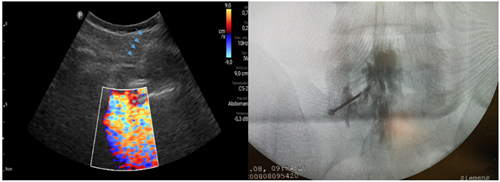

Pacientes y métodos: Un total de 25 pacientes con dolor radicular lumbosacro fueron seleccionados para recibir inyecciones epidurales interlaminares de esteroides en posición decúbito dorsal, utilizando la técnica ecoguiada en plano, en tiempo real, en eje corto o transversal. En todos los casos, un epidurograma de control fue realizado previo a la inyección de la solución de esteroides. El rendimiento de la técnica fue estudiado mediante la tasa de éxito de la misma, entendido como éxito a la obtención de un epidurograma sin necesidad de abandonar la técnica ecográfica en un tiempo menor a 10 minutos. El rendimiento del procedimiento fue estadísticamente evaluado por el método de la suma acumulativa (CUSUM), y la curva de aprendizaje aplicando este método fue construida.

Resultados: La distancia promedio desde la piel al complejo posterior evaluada por el escaneo ecográfico previo al procedimiento fue de 6,7 ± 1,8 cm. De los 25 procedimientos realizados, en 21 se alcanzó el espacio epidural sin ayuda de la fluoroscopia, en un tiempo promedio de 4,8 ± 1,2 minutos. Esto constituye una tasa de éxito del 84 %. En los cuatro procedimientos restantes el espacio epidural fue alcanzado con éxito mediante el uso complementario de la fluoroscopia.

Figura 1